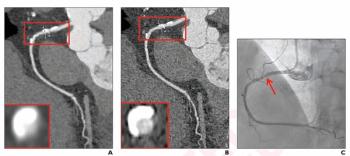

In a new study comparing standard resolution and ultra-high resolution modes for patients undergoing coronary CTA with photon-counting detector CT, researchers found that segment-level sensitivity and accuracy rates for diagnosing coronary artery stenosis were consistently > 89.6 percent.